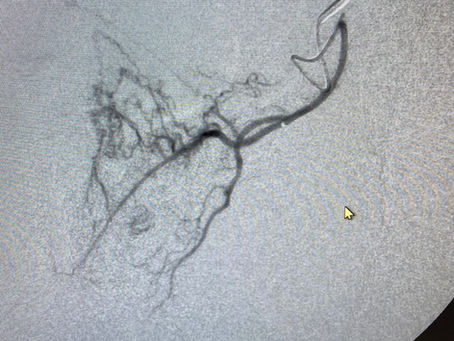

GAE is a new procedure, first developed in Japan, that treats knee pain from arthritis. It is similar to getting a steroid injection in the knee except that more reliably reduces pain and can keep the pain away for years instead of several months. It is performed by placing a tiny catheter into the artery at the top of the leg and guiding it down to the knee using x-ray. Images of the knee arteries are then taken that show where there are areas of inflammation that are causin

Uncommon Origins to the Prostatic Artery

In less than 1% of men, the prostatic artery will arise from the external iliac artery rather than from the internal iliac artery. This...